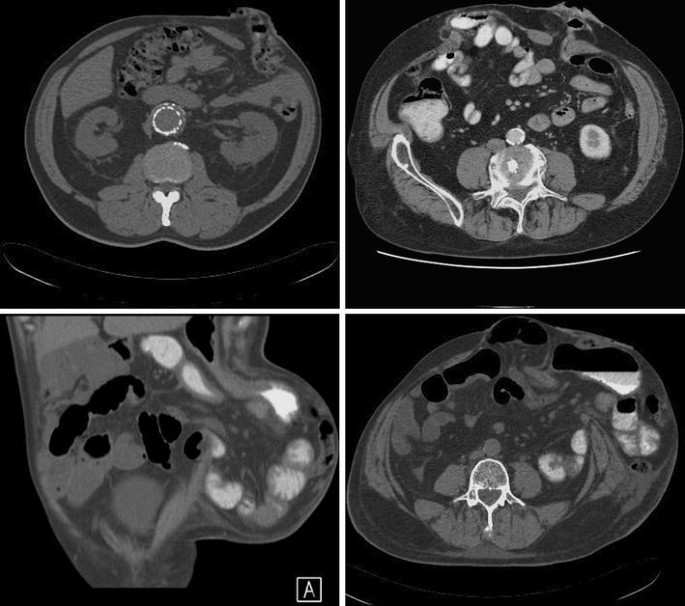

Previously published classifications on PH are based on three different examination methods: physical examination, intraoperative findings or radiological description (CT scans or US). According to the type of hernia and hernia content, we isolated four to five subgroups of hernias. These subgroups describe various pathological findings of the stoma: from the real hernias (with the presence of the hernia sac and its content) to the prolapse of the stoma or stoma loop protrusion under the skin [4–7]. Only the classification by Gil and Szczepkowski includes coexisting midline incisional hernias in the classification [8]. Table 1 summarises all published classifications. Table 2 summarises the subgroup definitions of different classifications.

As in previously published inguinal and ventral hernia and parastomal classifications, the measurements of the hernia orifice and cIH are performed intraoperatively. The measure of the hernia orifice should follow the general roles of previously published EHS classification of incisional hernias (aggregate length and width of all defects on previous scar [1], but the size of the parastomal defect separately). We agree that although CT scans could be performed preoperatively and could help determine the subgroup of the defect, intraoperative measurement is the recommended procedure.

Moreno-Matias J et al (2009) The prevalence of parastomal hernia after formation of an end colostomy. A new clinico-radiological classification. J Colorectal Dis 11:173–177

Seo HS, Kim HJ, Sy Oh, Lee JH, Suh KW (2011) Computed tomography classification for parastomal hernia. J Korean Surg Soc 81:111–114